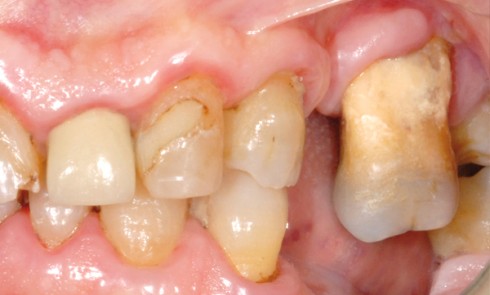

Article réservé à nos abonnés Choix d’une approche additive dans les traitements d’usures érosives et attritives : intérêts des full mock up

Les patients atteints d’érosion/usure de nature chimique consultent de manière quasi exponentielle au sein des cabinets, avec des degrés d’atteinte...